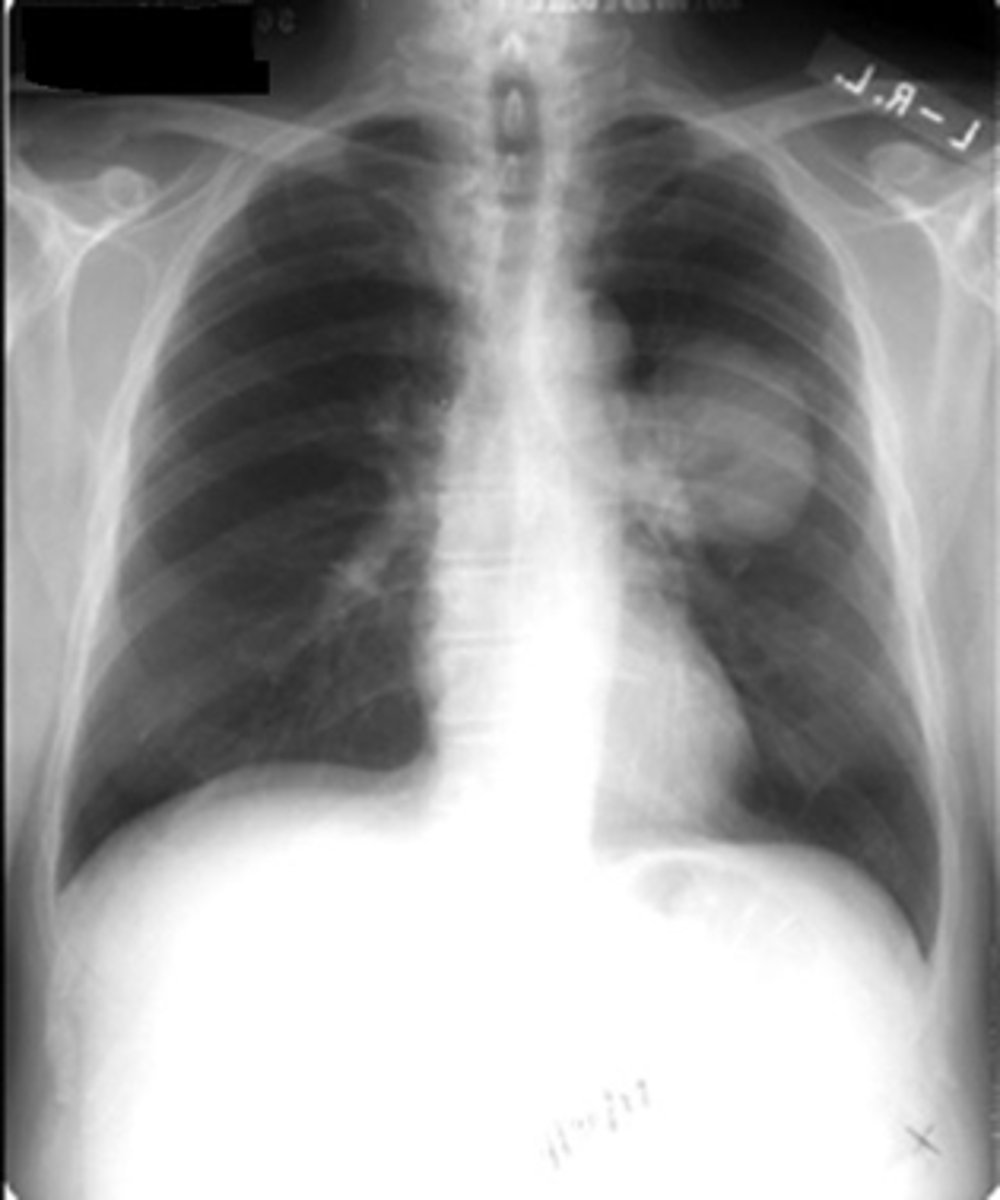

Lung cancer- adenocarcinoma